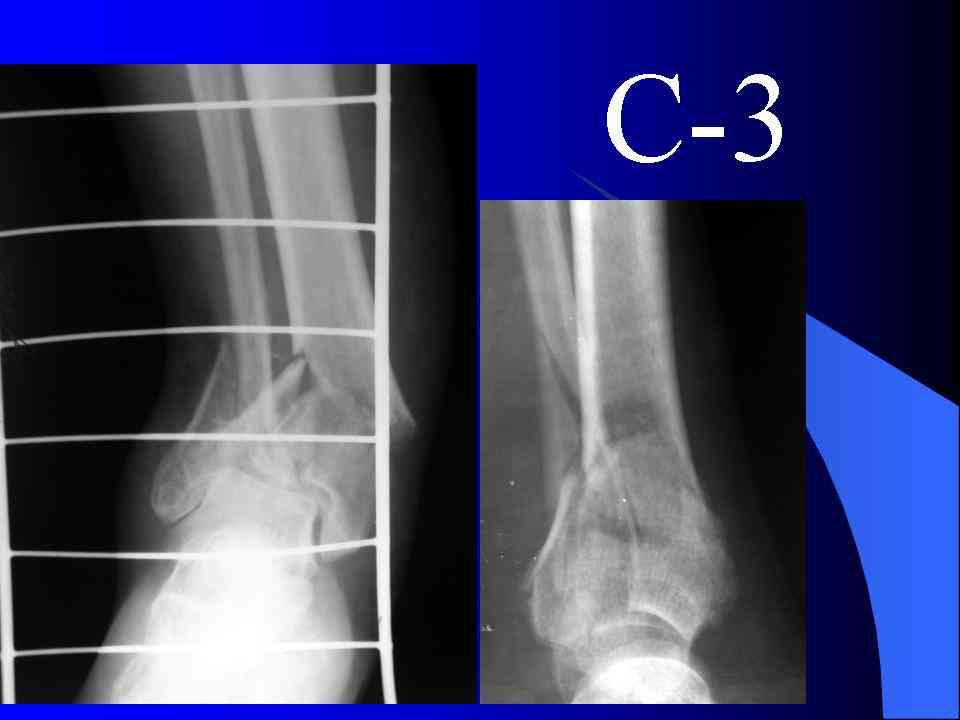

Это типичный перелом пилона, который надп лечить только открыто.Извини те что опоздал к обсуждению, но даже если вы уже оперировали больного по Илизарову это даже лучше.Посылаю картинки.

На рентгенограммах типичный перелом пилона по типу С-3. есть опыт до 100 открытых опреаций у нас в клинике. 20 примерно в год. Принцип один -все внутрисуставные переломы нуждаются в открытой репозиции и внутренней стабильной фиксации. При поступлении КТ не надо, так как получается только нагромождение костей. Истинной картины нет. Главное восстановить длину малоберцовой кости - это ключ к успеху. При поступлении меньше всего надо думать о сосудистых расстройствах, т.к. сама операция и репозиция даже сначала частичная даёт улучшение сосудитых нарушений. Причём очень быстро. Операция в 2этапа. При поступлении доступ позади наружной лодыжки, причём обязательно. После этого репозиция малоберцовой кости и фиксация пластиной 1/3 трубки под винт 3,5. Дренаж и любой аппарат наружной фиксации. Затем после спадения отёка на 5-7-10 день аппрат снимается и дугообразный разрез спереди от медиальной лодыжки 10-12 см. Главной чтобы расстояние между 1 и вторым разрезом было не меньше 7-8 см. Тогда не будет некрозов лоскутов. Таранная кость используется как матрица на неё укладываются отломки и фиксируются пицами. Ренг-контроль. Отломки лежат все отдельно, но ничего не высыпется. При переломах С-3 всегда нужна костная пластика (из крыла). Фиксация пластиной лист клевера простой или LCP. Гипс не нужен. Дренаж до 48 часов. Операция длится 3-4 часа обязательно без жгута. Посылаю примерно такой же случай.

Посылаю результат лечения предыдущего больного через год.